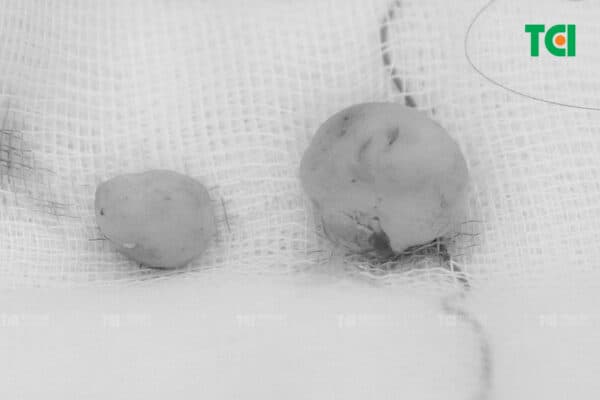

Trường hợp của anh Q., từ lúc lỗ xỏ khuyên sưng, đau đến khi khối bất thường lớn khoảng 1cm, chỉ mất chưa đầy 1 tháng. Để bảo tồn nguyên vẹn 2 tai, anh Q. được bác sĩ TCI chỉ định phẫu thuật ngay sau thăm khám. Với quy trình phẫu thuật 4 bước: khử trùng, gây tê tại chỗ, phẫu thuật, khâu vết mổ; 30 phút, bác sĩ TCI đã loại bỏ thành công 2 sẹo lồi, anh Q. có thể về nhà ngay sau đó.

30 phút, bác sĩ TCI đã loại bỏ thành công 2 sẹo lồi cho anh Q.